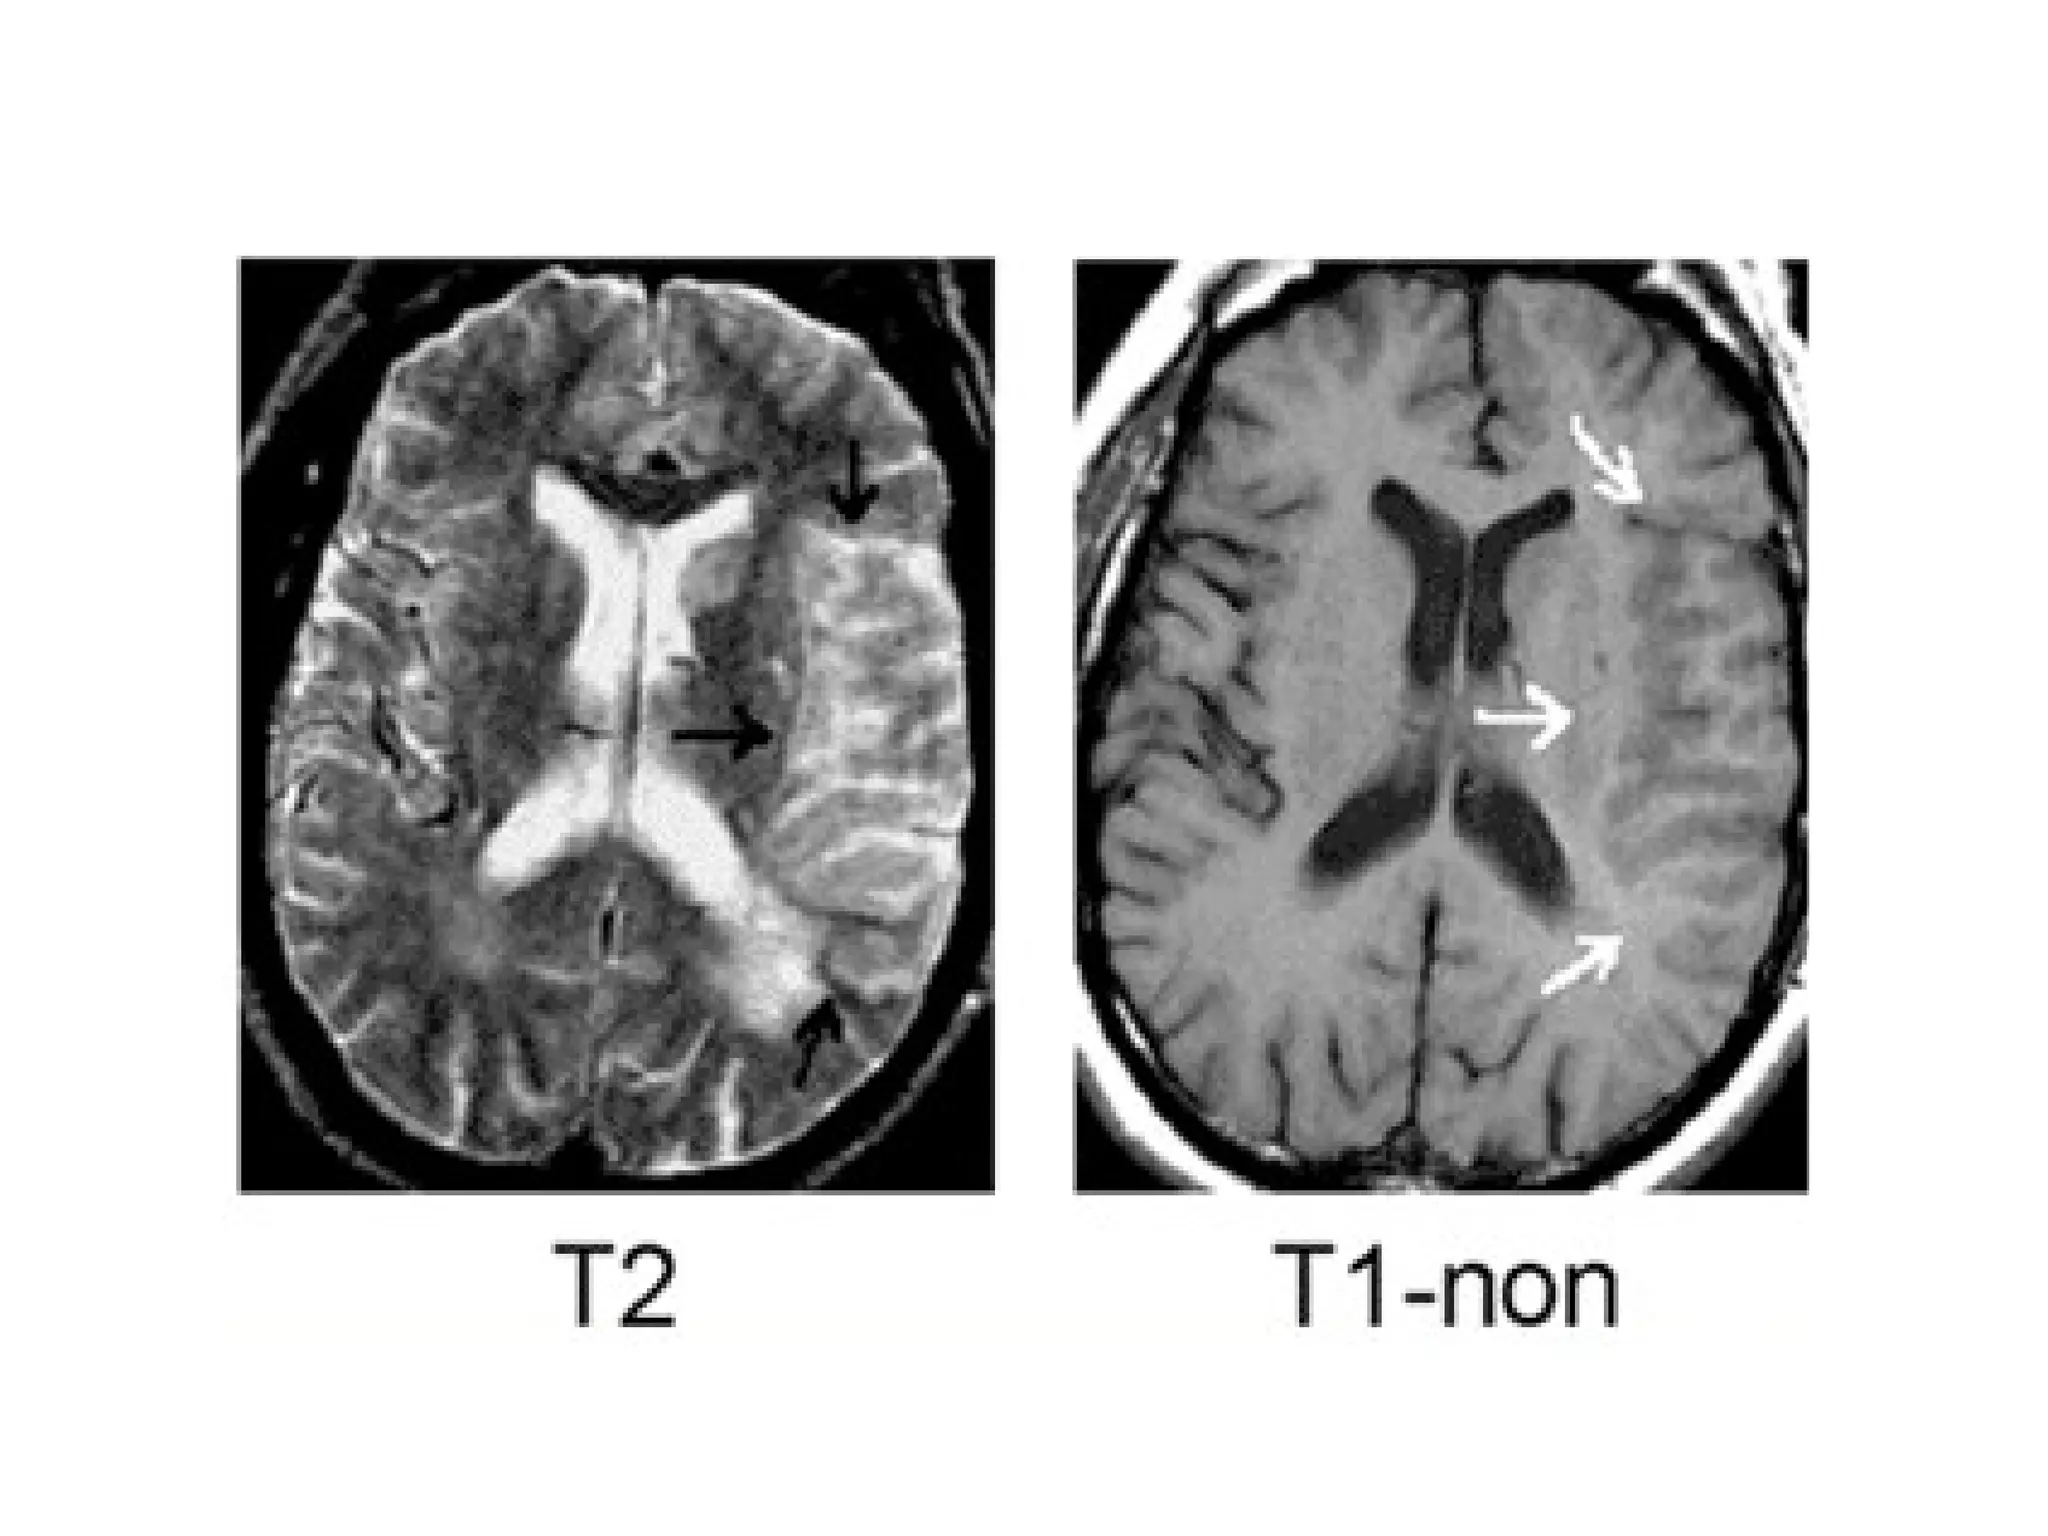

(Left) T2 and diffusion (Right) showing bilateral thalamic infarcts